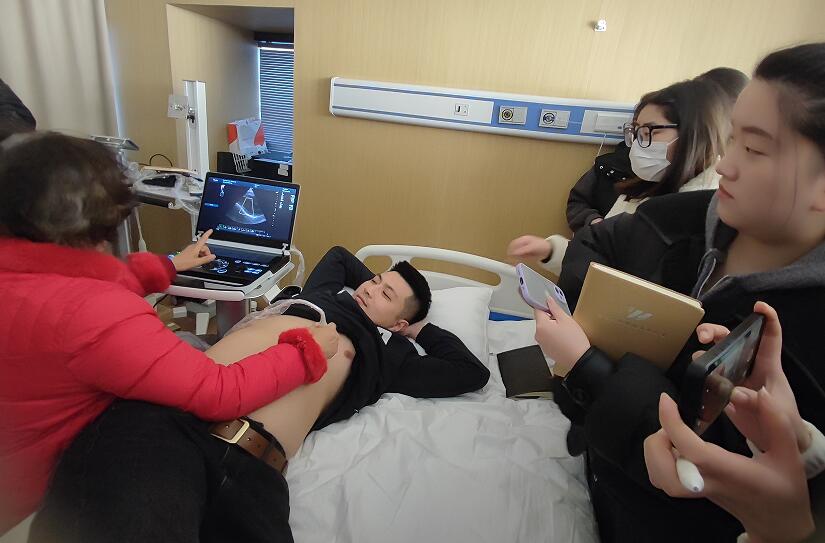

当天的超声培训现场气氛热烈非凡,来自普迈思医疗事业部的同仁们纷纷积极参与,满怀期待地聚集在讲台周围,他们的眼神充满了对新知识的渴望和对技术提升的执着追求。老师身边里三层外三层围满了学员,大家或是聚精会神聆听讲解,或是踊跃提问,交流互动,浓厚的学习氛围让整个场地显得热闹非凡,尽管空间狭小,但阻挡不住的是每一位参与者内心深处对于专业技能提升的决心与毅力。

授课的专家老师被这股澎湃的学习热情深深打动,她的脸上洋溢着欣慰和鼓舞的笑容。面对这样一群如饥似渴的学子,老师更是倾尽全力,毫无保留地将自己丰富的临床经验和深厚的专业理论知识悉数传授,详细解答每一个问题,用心指导每一次操作演练。她表示,普迈思医疗事业部团队展现出的这种敬业精神和积极向上的风貌让她深受感染,还给予了他们高度评价和嘉许。